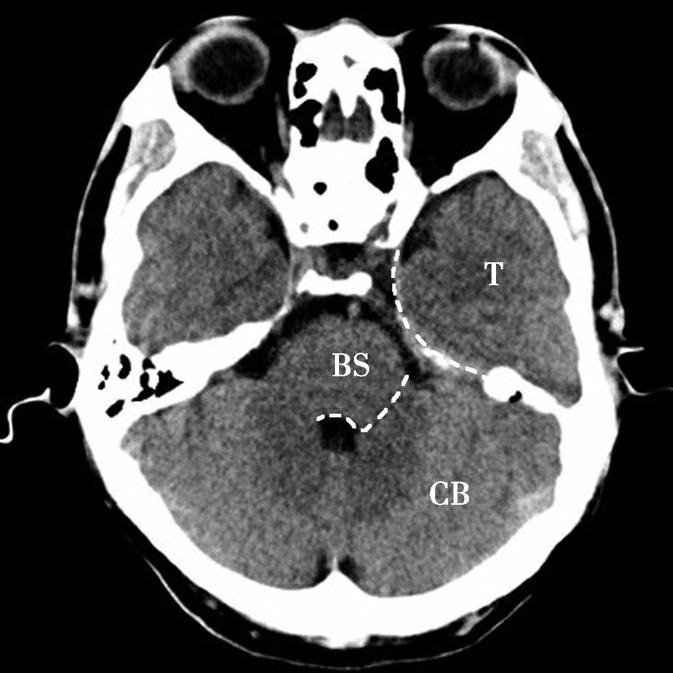

图1-2-7 脑叶划分示意图

CB.小脑;BS.脑干;T.颞叶

蝶骨体占据层面中部,内部可见蝶窦,中间有骨性分隔。蝶骨体前方正中为鼻中隔,鼻中隔两侧为蜂窝状含气骨性腔隙,即筛窦,筛窦前方为鼻骨。筛窦两侧可见两侧对称的圆形眼球断面位于眼眶内,眼球壁呈厚薄均匀的环状,称为眼环。玻璃体位于眼环内呈均匀低密度影,晶状体位于玻璃体前方,呈双凸透镜状高密度影,眼球后方为锥体形的眶脂体,其内正中可见视神经通行,眶内侧壁与筛窦间隔以菲薄的纸板,眶外侧壁由额骨眶突和蝶骨大翼构成,内、外直肌紧贴眶壁走向眶尖,视神经管位于眶尖。位于蝶窦两侧的有颞叶、颞骨鳞部及颞骨外侧的颞肌。蝶窦后方为斜坡,斜坡后外侧为颞骨岩部尖,后外方为乳突,其内可见乳突小房呈蜂窝状,岩部的内后缘可见两侧对称的内听道,其内第Ⅶ、Ⅷ对脑神经CT上无法分辨,听神经瘤常伴有内听道的扩大(图1-2-8)。内听道后外方的骨性空腔为中耳鼓室。枕骨斜坡及岩骨后方为颅后窝,脑桥位于其前部,脑桥后方可见第四脑室,其后方为小脑蚓部。小脑半球以小脑中脚与脑桥相连,脑桥与斜坡之间为桥前池,其向两侧延伸的部分呈三角形,两侧对称,位于脑桥、小脑中脚及岩骨之间,称为脑桥小脑角池。位于脑桥小脑角池的常见病变有听神经瘤、三叉神经瘤、脑膜瘤和胆脂瘤等(图1-2-9)。